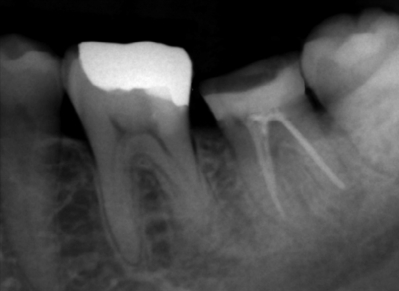

下顎左側第二大臼歯に対する根管充塡終了後のエックス線写真を別に示す。鋳造体を用いた支台築造を行う際、築造体の保持力を高めるのに有効なのはどれか。1つ選べ。